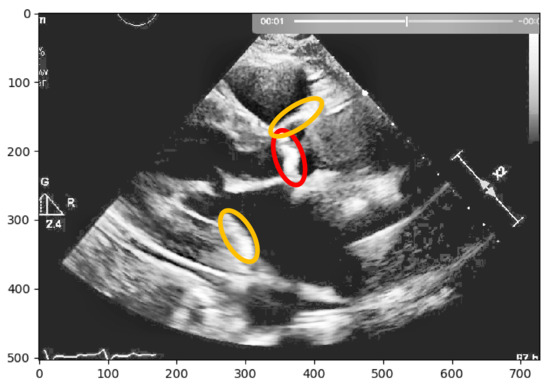

In a second approach, a Region-based Segmentation [20] was attempted, where the aim was to segment different objects (calcium/non-calcium) by analyzing their pixel values. This technique classifies the pixels—based on a threshold applied to each pixel value—as an object or background. Moreover, since we may have multiple objects—given that calcium can go from severe to none in different scale values—multiple thresholds were initially defined to segment multiple objects, as represented by Figure 2. However, if we have an image with no significant grayscale difference, this approach will fail to get accurate segments. To mitigate this issue, another approach was attempted to have a more comprehensive and interpretable image. An Edge Detection algorithm [21] was used where the pixel brightness is scaled to an embossed image, where the height of each “mountain” corresponds to the pixel brightness. Figure 3 shows us the application of Edge Detection on an echocardiography image of the left ventricle. This approach turned out to be redundant since it represents the pixel values by “mountains heights”. This could be immediately calculated if the first step were extracting the pixel’s exact value and minimizing computation time. Otherwise, after implementing this algorithm, it would be another one would be needed to find each “mountain” height.

Figure 2. Echocardiography image with region-based segmentation.